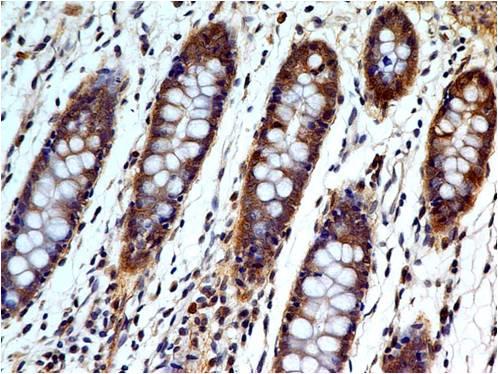

Fig. 1: Formalin-fixed, paraffin-embedded human Pancreatic Carcinoma stained with MRP3 Mouse Monoclonal Antibody (ABCC3/2971).

Immunohistochemistry (Formalin-fixed) (1-2ug/ml for 30 minutes at RT)(Staining of formalin-fixed tissues requires heating tissue sections in 10mM Tris with 1mM EDTA, pH 9.0, for 45 min at 95°C followed by cooling at RT for 20 minutes)